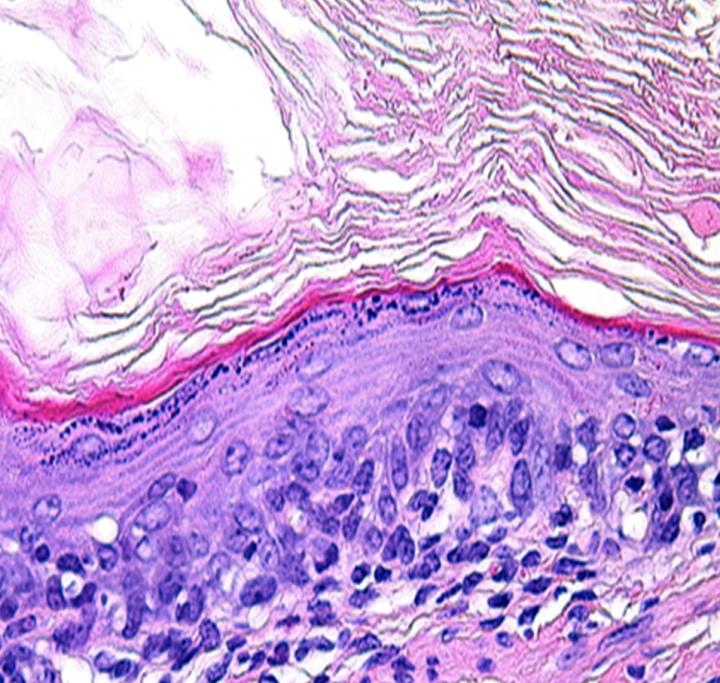

In a first step toward future human therapies, researchers at The Saban Research Institute of Children's Hospital Los Angeles have shown that esophageal tissue can be grown in vivo from both human and mouse cells. The study has been published online in the journal Tissue Engineering, Part A .

The tissue-engineered esophagus formed on a relatively simple biodegradable scaffold after the researchers transplanted mouse and human organ-specific stem/progenitor cells into a murine model, according to principal investigator Tracy C. Grikscheit, MD, of the Developmental Biology and Regenerative Medicine program of The Saban Research Institute and pediatric surgeon at Children's Hospital Los Angeles.

Progenitor cells have the ability to differentiate into specific types of cell, and can migrate to the tissue where they are needed. Their potential to differentiate depends on their type of "parent" stem cell and also on their niche. The tissue-engineering technique discovered by the CHLA researchers required only a simple polymer to deliver the cells, and multiple cellular groupings show the ability to generate a replacement organ with all cell layers and functions.

"We found that multiple combinations of cell populations allowed subsequent formation of engineered tissue. Different progenitor cells can find the right 'partner' cell in order to grow into specific esophageal cell types – such as epithelium, muscle or nerve cells – and without the need for exogenous growth factors. This means that successful tissue engineering of the esophagus is simpler than we previously thought," said Grikscheit.

"We have demonstrated that a simple and versatile, biodegradable polymer is sufficient for the growth of tissue-engineered esophagus from human cells," added Grikscheit. "This not only serves as a potential source of tissue, but also a source of knowledge, as there are no other robust models available for studying esophageal stem cell dynamics. Understanding how these cells might behave in response to injury and how various donor cell types relate could expand the pool of potential donor cells for engineered tissue."